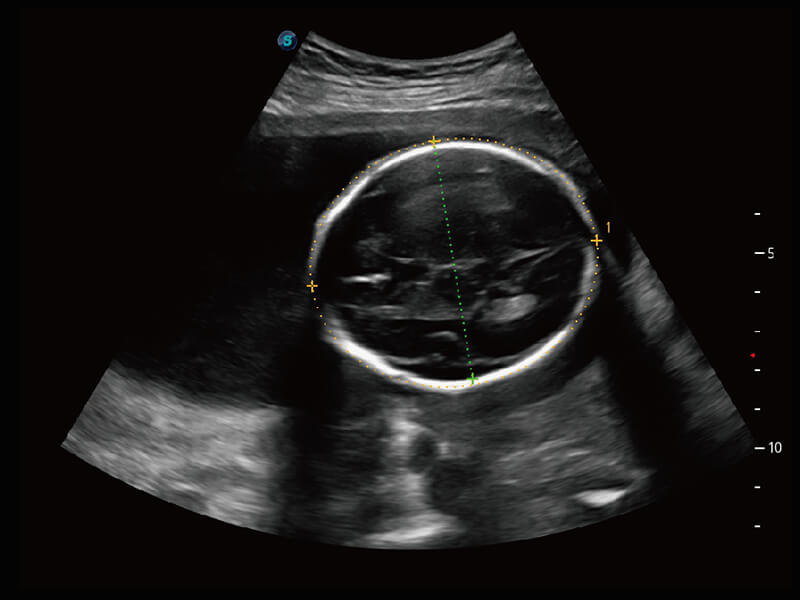

S60探头工艺,从前端信号处理每一个环节采集无损声学数据,真实还原组织原貌,再现解剖细节。

S-Fetus 产科扫查助手

• 缩短

操作时间

• 提升

准确率

• 单次

按键操作